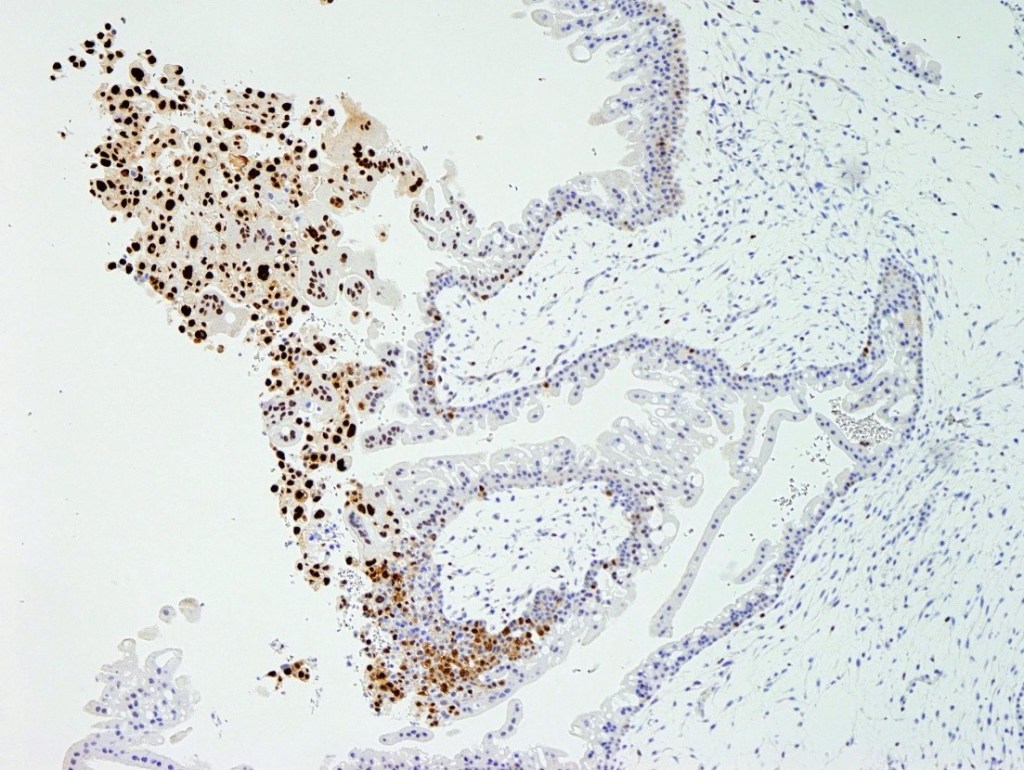

- P57 (maternally expressed paternally imprinted) is negative in the villous stroma and trophoblasts (figure 7).